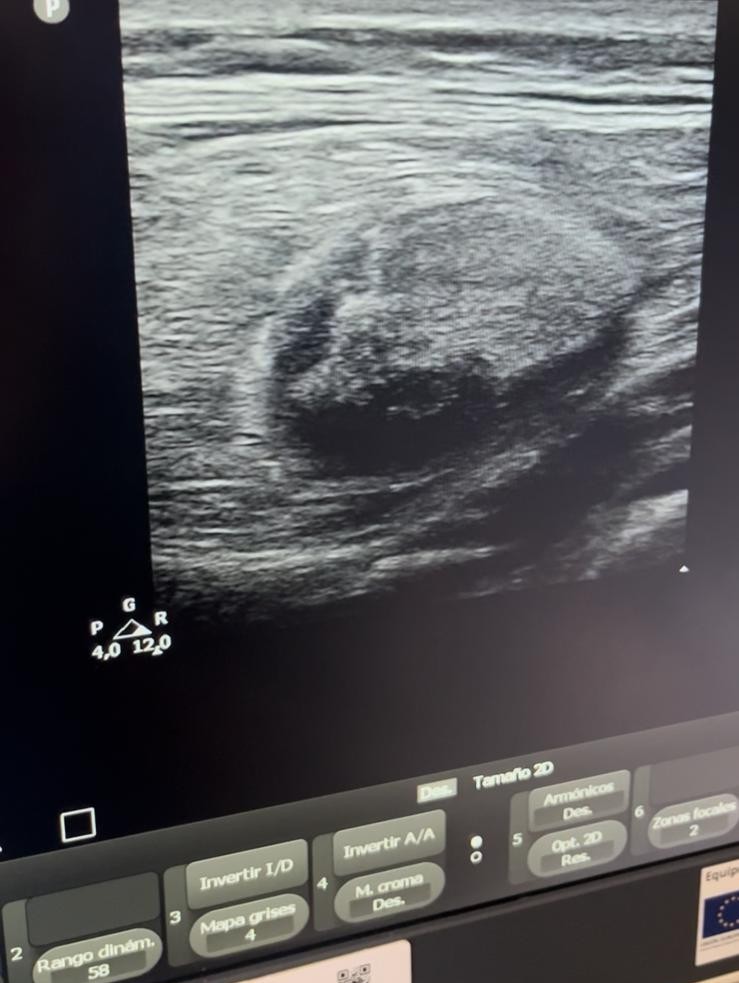

Hallazgos ecográficos

Ecografía clínica con sonda lineal: lesión mal definida, heterogénea, con áreas hiperecogénicas e hipoecoicas, vascularizada, de aproximadamente 5x7cm, sospechosa de malignidad.